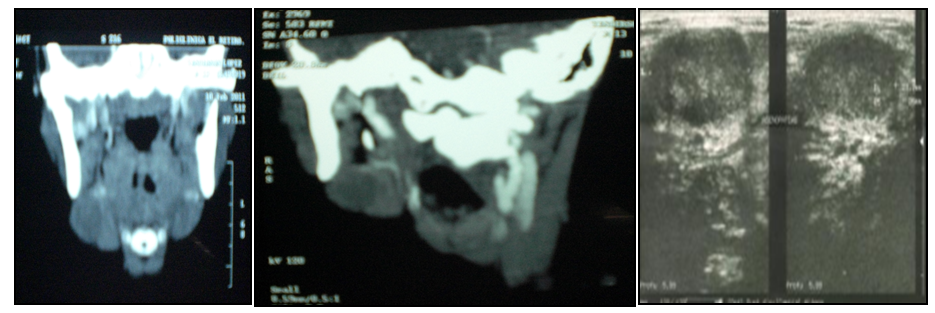

Image studios (cervical sonogram and CT scan) reported: Increased volume of the submandibular gland on the right side with impaired surrounding fat, with displacement of the cervical fascia.

Cervical bilateral lymphadenopathy predominantly located below sternocleidomastoid and submandibular location. There is a small plastron of about 2cm in the cervical chains on the right side behind and below the ipsilateral sternocleidomastoid (Figures 2). Subsequently, ultrasound soft tissue neck region, described, three images of nodular, adjacent hypoechoic aspect of regular shape, the larger diameter 2,7cm and two of 1.3 and 1.7cm. Left submaxillary region: two similar nodes of that measured 1.5 and 1.2 cm in diameter (Figure 3) were observed.

Figure 2 There is a small plastron of about 2 cm in the cervical chains on the right side behind and below the ipsilateral sternocleidomastoid.

Figure 3 Preoperative studies were normal. Puncture is performed with fine needle whose cytology report concludes.